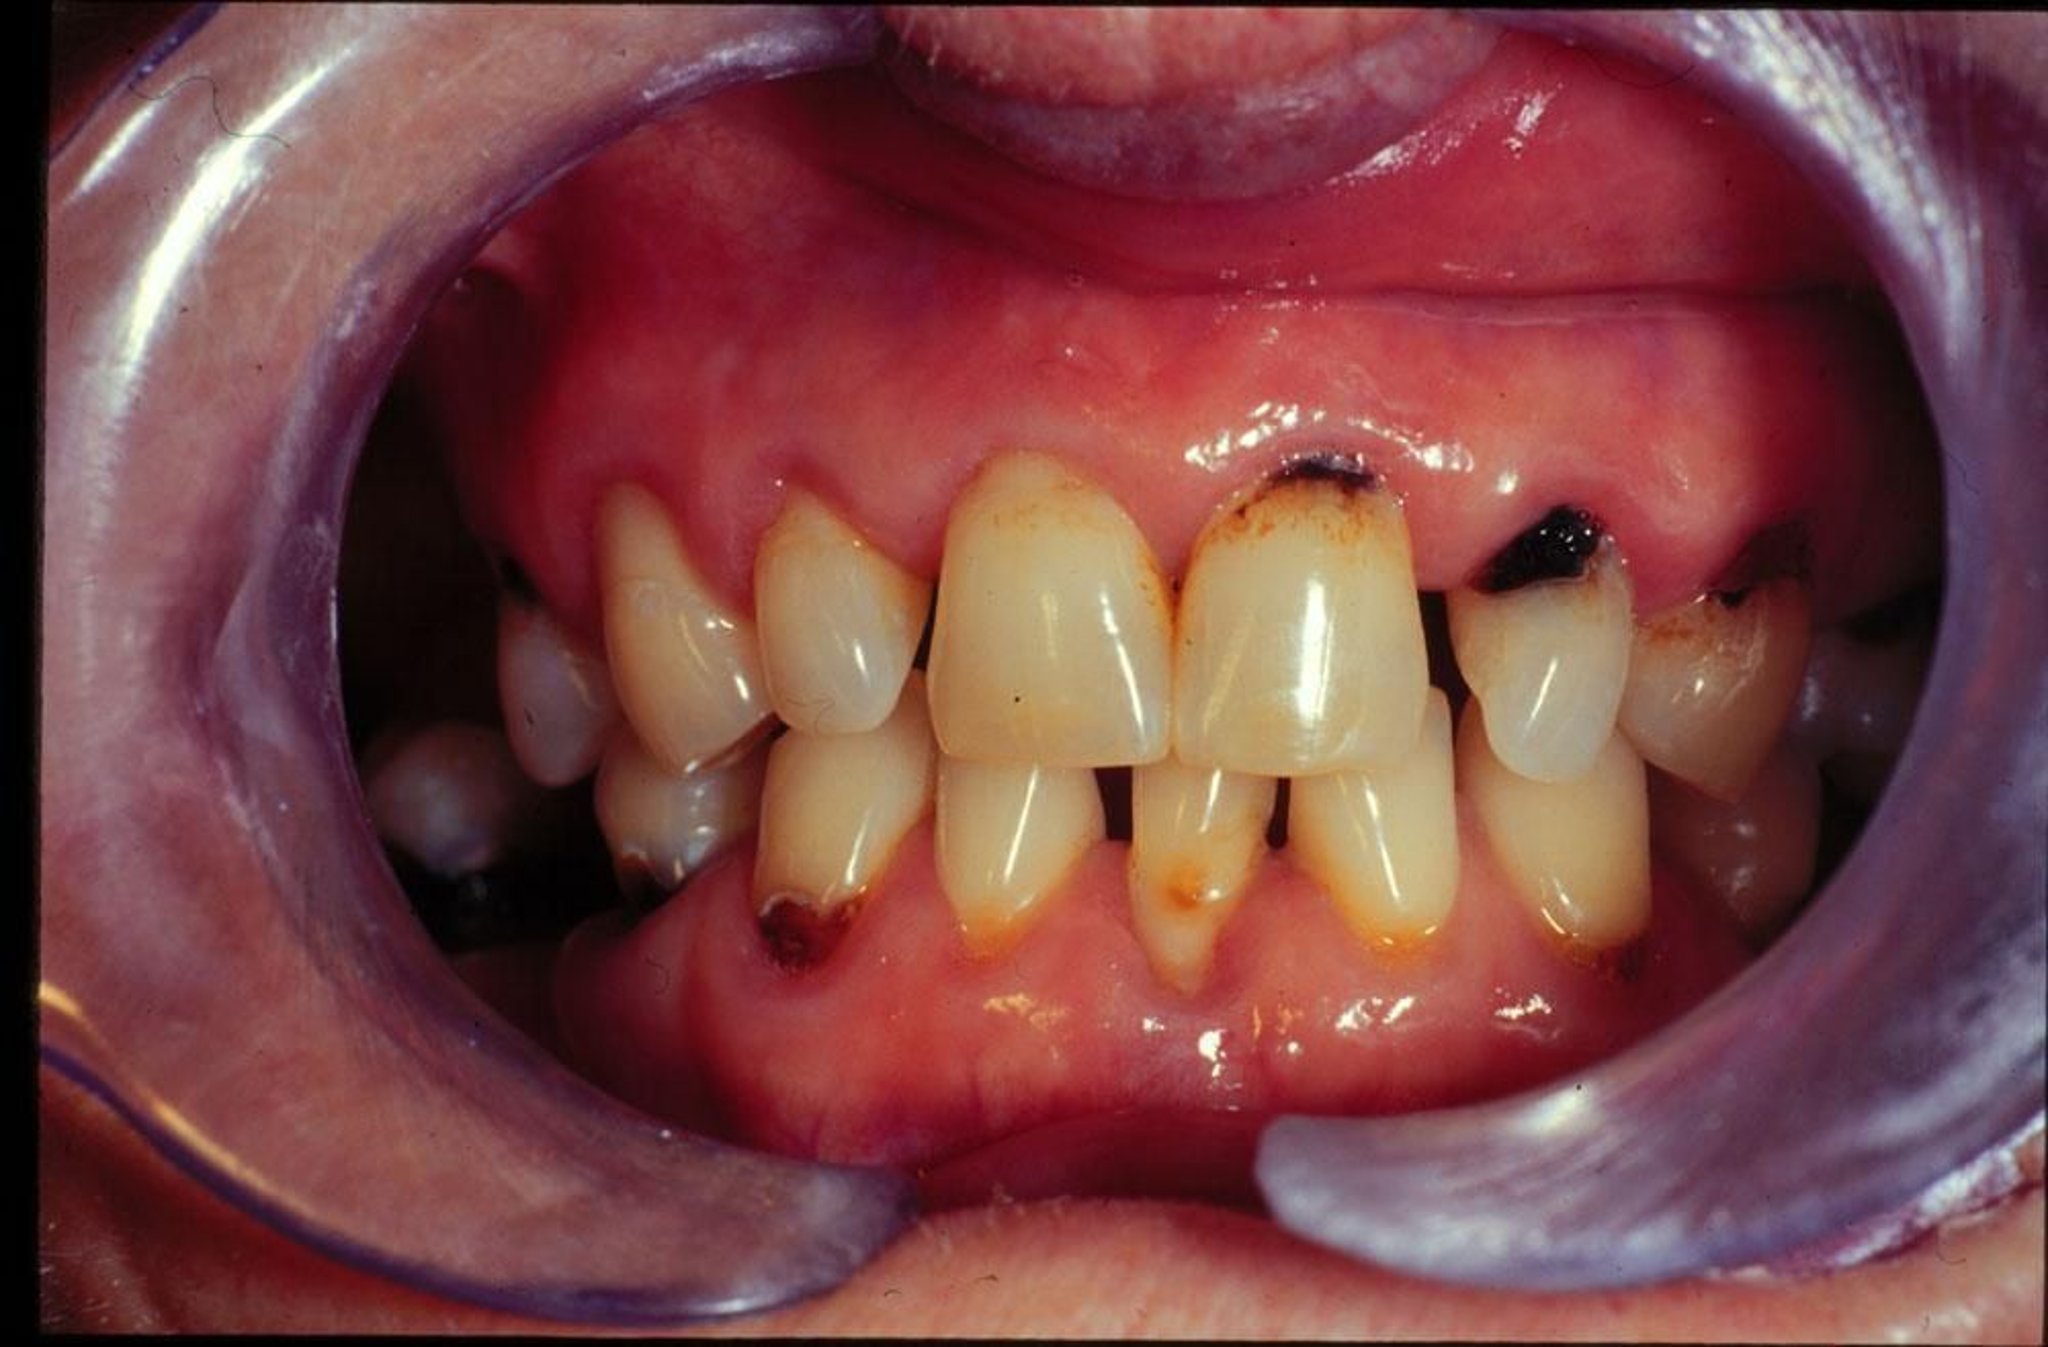

تُظهر هذه الصورة نخورًا سنية حديثة وناكسة عند شخص مصاب بجفاف في الفم.

Image provided by Jonathan A.Ship, DMD.